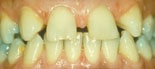

tänder som sitter snett Dentala_anomalier_efter

Före behandling Efter behandling

Med dental anomali menas att enskilda tänder är tippade eller roterade. Tänder som inte kommit fram, trots att anlaget finns, är också vanligt förekommande.